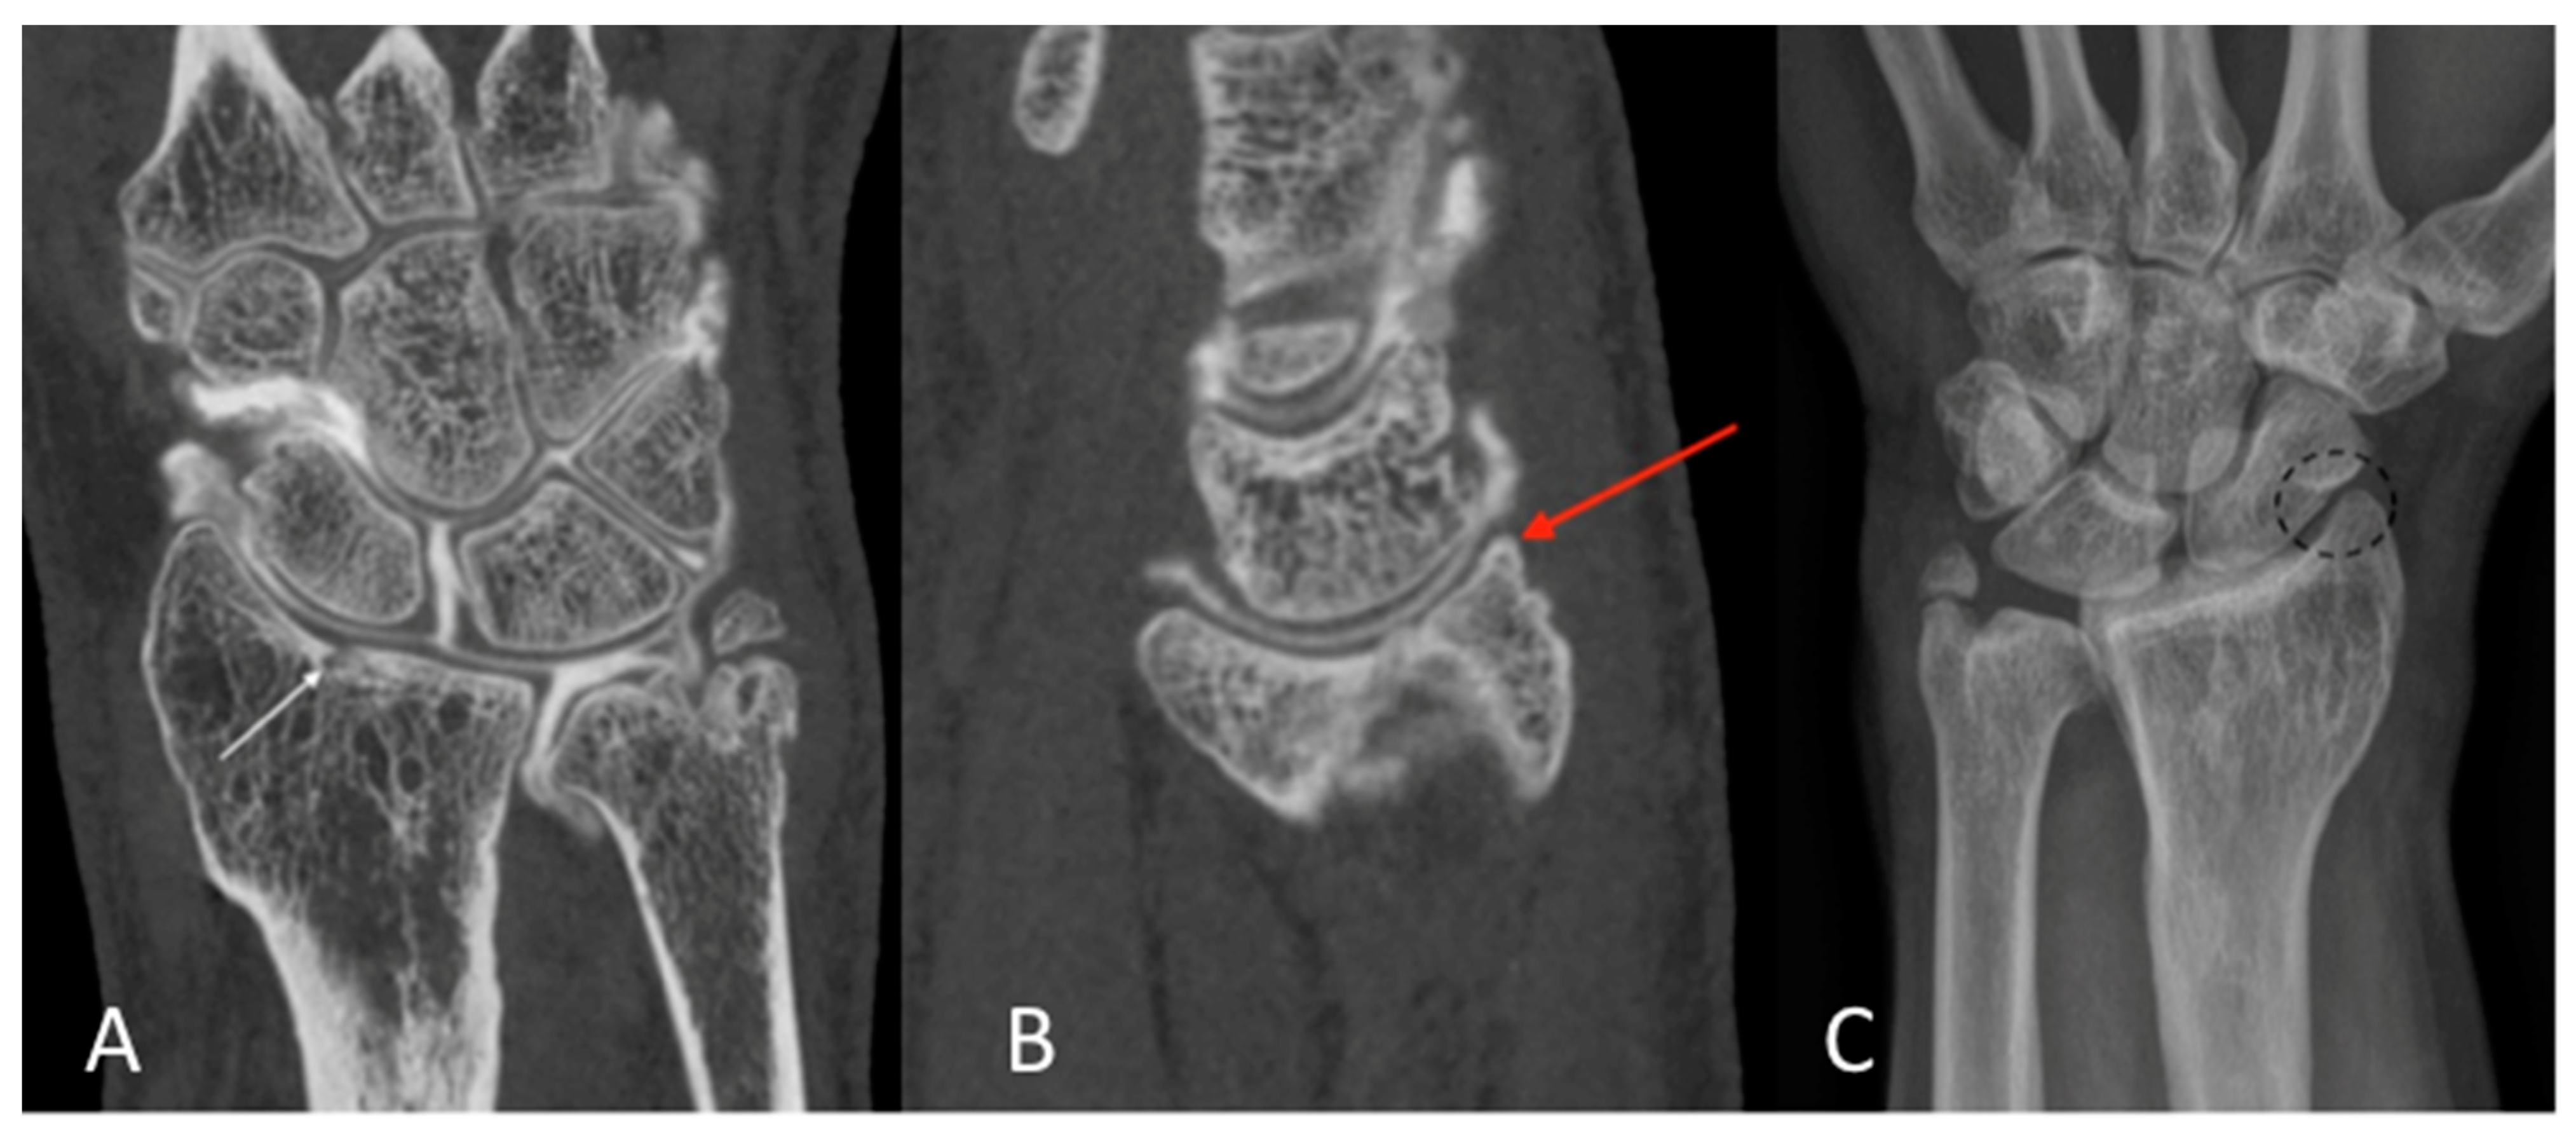

Figure 4. The HU numbers of all 32 CBCT-As were analyzed in the coronal plane after the application of MBIR2. Here, an example of a right knee is shown. The HUs for CM, trabecular and cortical sub chondral bone, and for cartilage densities were reported. ROIs were also placed with three measurements for every item (A). The MJW was evaluated with the MJW at the lateral and medial side of the femoro-tibial joint (B). HU: Hounsfield unit; CBCT-A: cone-beam computed tomography arthrography; ROI: region of interest; MJW: mean joint width; CBCT: cone-beam computed tomography; MDCT: multi-detector computed tomography.

2.4. Quantitative Image Analysis of CBCT-A

The correspondence between electronic densities and the HU was evaluated using a standardized CIRS-062MA (Norkfold, VA, USA) phantom (Figure 3) for the CBCT images reconstructed with the two available reconstruction algorithms: MBIR 1 and MBIR2. The results were compared to the HU obtained from the two MDCT (SOMATOM Definition Flash Siemens Healthcare and Discovery 750 HD GE Healthcare) available in our department. The phantom comprises nine inserts with different materials corresponding to different electronic densities (Figure 3A). The reproducible region of interest (ROI) (size and seat) was placed in all nine inserts (Figure 3B), with three measurements for every item. Then, we analyzed the HU for all 32 CBCT-As in the coronal plane for the CM, trabecular subchondral bone, cortical bone, and cartilage densities after application of the MBIR2. ROIs were also placed in all cases, with three measurements for every item (Figure 4A). The mean was reported for statistical analysis.

Finally, MJWs were calculated, of the lateral and medial sides for the knee and center of the radio-carpal joint in the wrist or talocrural joint in the ankle, the tibio-talar joint in the ankle, and the femoro-tibial joint in the knee (Figure 4B), and compared with the corresponding DR images.

Table 4 summarizes the results obtained from the calibration of the HU with the standardized phantom. Measurements in both the MDCT (Siemens and GE) revealed similar densities in all tissues analyzed. For CBCT, the HU did not correspond to the usual values obtained for the MDCT, with a greater mean deviation obtained with the CT HU for the MBIR1 than for MBIR2. The mean HU calculated for the CBCT-A was 1966 for CM, 328 for trabecular bone, 812 for the subchondral cortex, and 330 for cartilage. We focused on bone density, as no normal values were found in the literature for cartilage; regarding CM, the contrast was diluted with the joint effusion in many cases. We noticed that the HU of CBCT-A measured for trabecular bone and cartilage were similar and corresponded to the bone density values of 200 mg/cc for the MDCT, with either MBIR1 or MBIR2 (236-298HU). The HU of subchondral cortical bone based on CBCT-A was similar to the HU of bone with a density of 80 mg/cc based on MDCT, particularly with MBIR2 (Table 4).